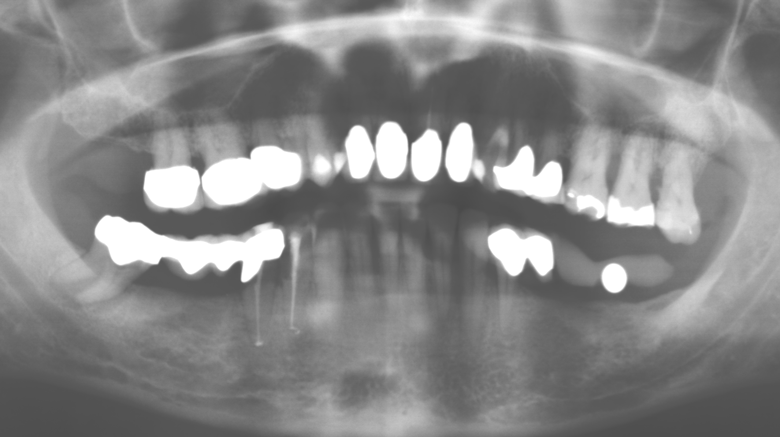

Fig. 1: Radiografia panoramica della situazione iniziale nel Panoramic radiograph of initial situation in 2004.

Fig. 1: Radiografia panoramica della situazione iniziale nel 2004.

Un paziente di 52 anni si è presentato nella nostra clinica per la prima volta nel 2004 a seguito della perdita dei denti nel terzo quadrante, esprimendo il desiderio di un nuovo restauro protesico. La diagnostica parodontale e radiologica ha rivelato la necessità di un ampio trattamento parodontologico. Inoltre, ai denti 48, 28 e 27 è stata attribuita una prognosi molto scarsa e sono stati successivamente estratti (Fig. 1). A seguito del trattamento periodontologico sistematico completato con successo, è stato inserito una protesi dentale fissa con l'inserimento di cinque impianti nelle regioni dentali 35, 36, 37, 46 e 47. Il trattamento protesico dei denti naturali è stato effettuato con corone rivestite in ceramica di biossido di zirconio; gli impianti two-piece composti da abutment singoli in biossido di zirconio e corone similmente rivestite in ceramica di biossido di zirconio (base Cercon colorata, Dentsply Sirona Lab). L'inserimento definitivo del restauro protesico è avvenuto nel 2005.

Il controllo decennale non ha rivelato alcuna indicazione dell'avanzamento della perdita di attaccamento clinico o della perdita di sostanza ossea perimplantare (Fig. 3).

Fig. 3: Radiografia panoramica dopo dieci anni con impianti.